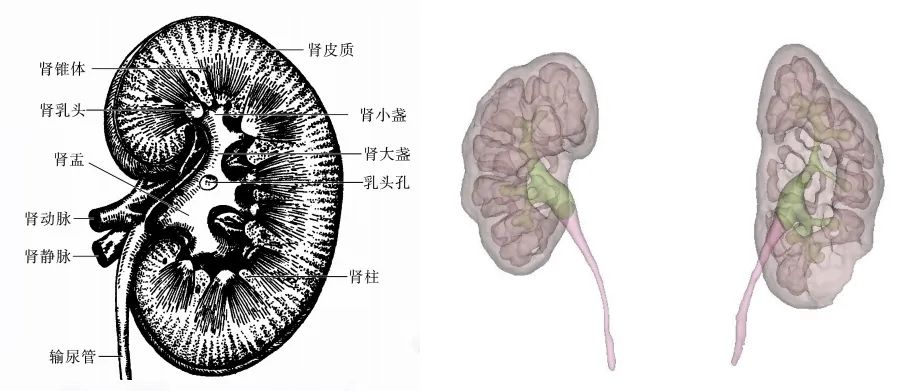

肾脏为成对的蚕豆状器官,位于脊柱两侧,属于泌尿系统中的一部分,负责过滤血液中的杂质、维持体液和电解质的平衡,最后产生尿液经尿道排出体外。

传统二维影像难以全面展示肾动脉分支、静脉变异及集合系统分布等空间关系,而这对肾肿瘤手术规划至关重要。